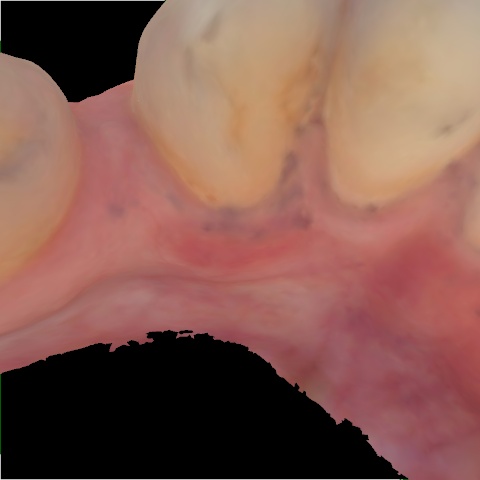

Image 59 / 400

NHD20794

Annotated as "Bad"

Original Image Rendering Image